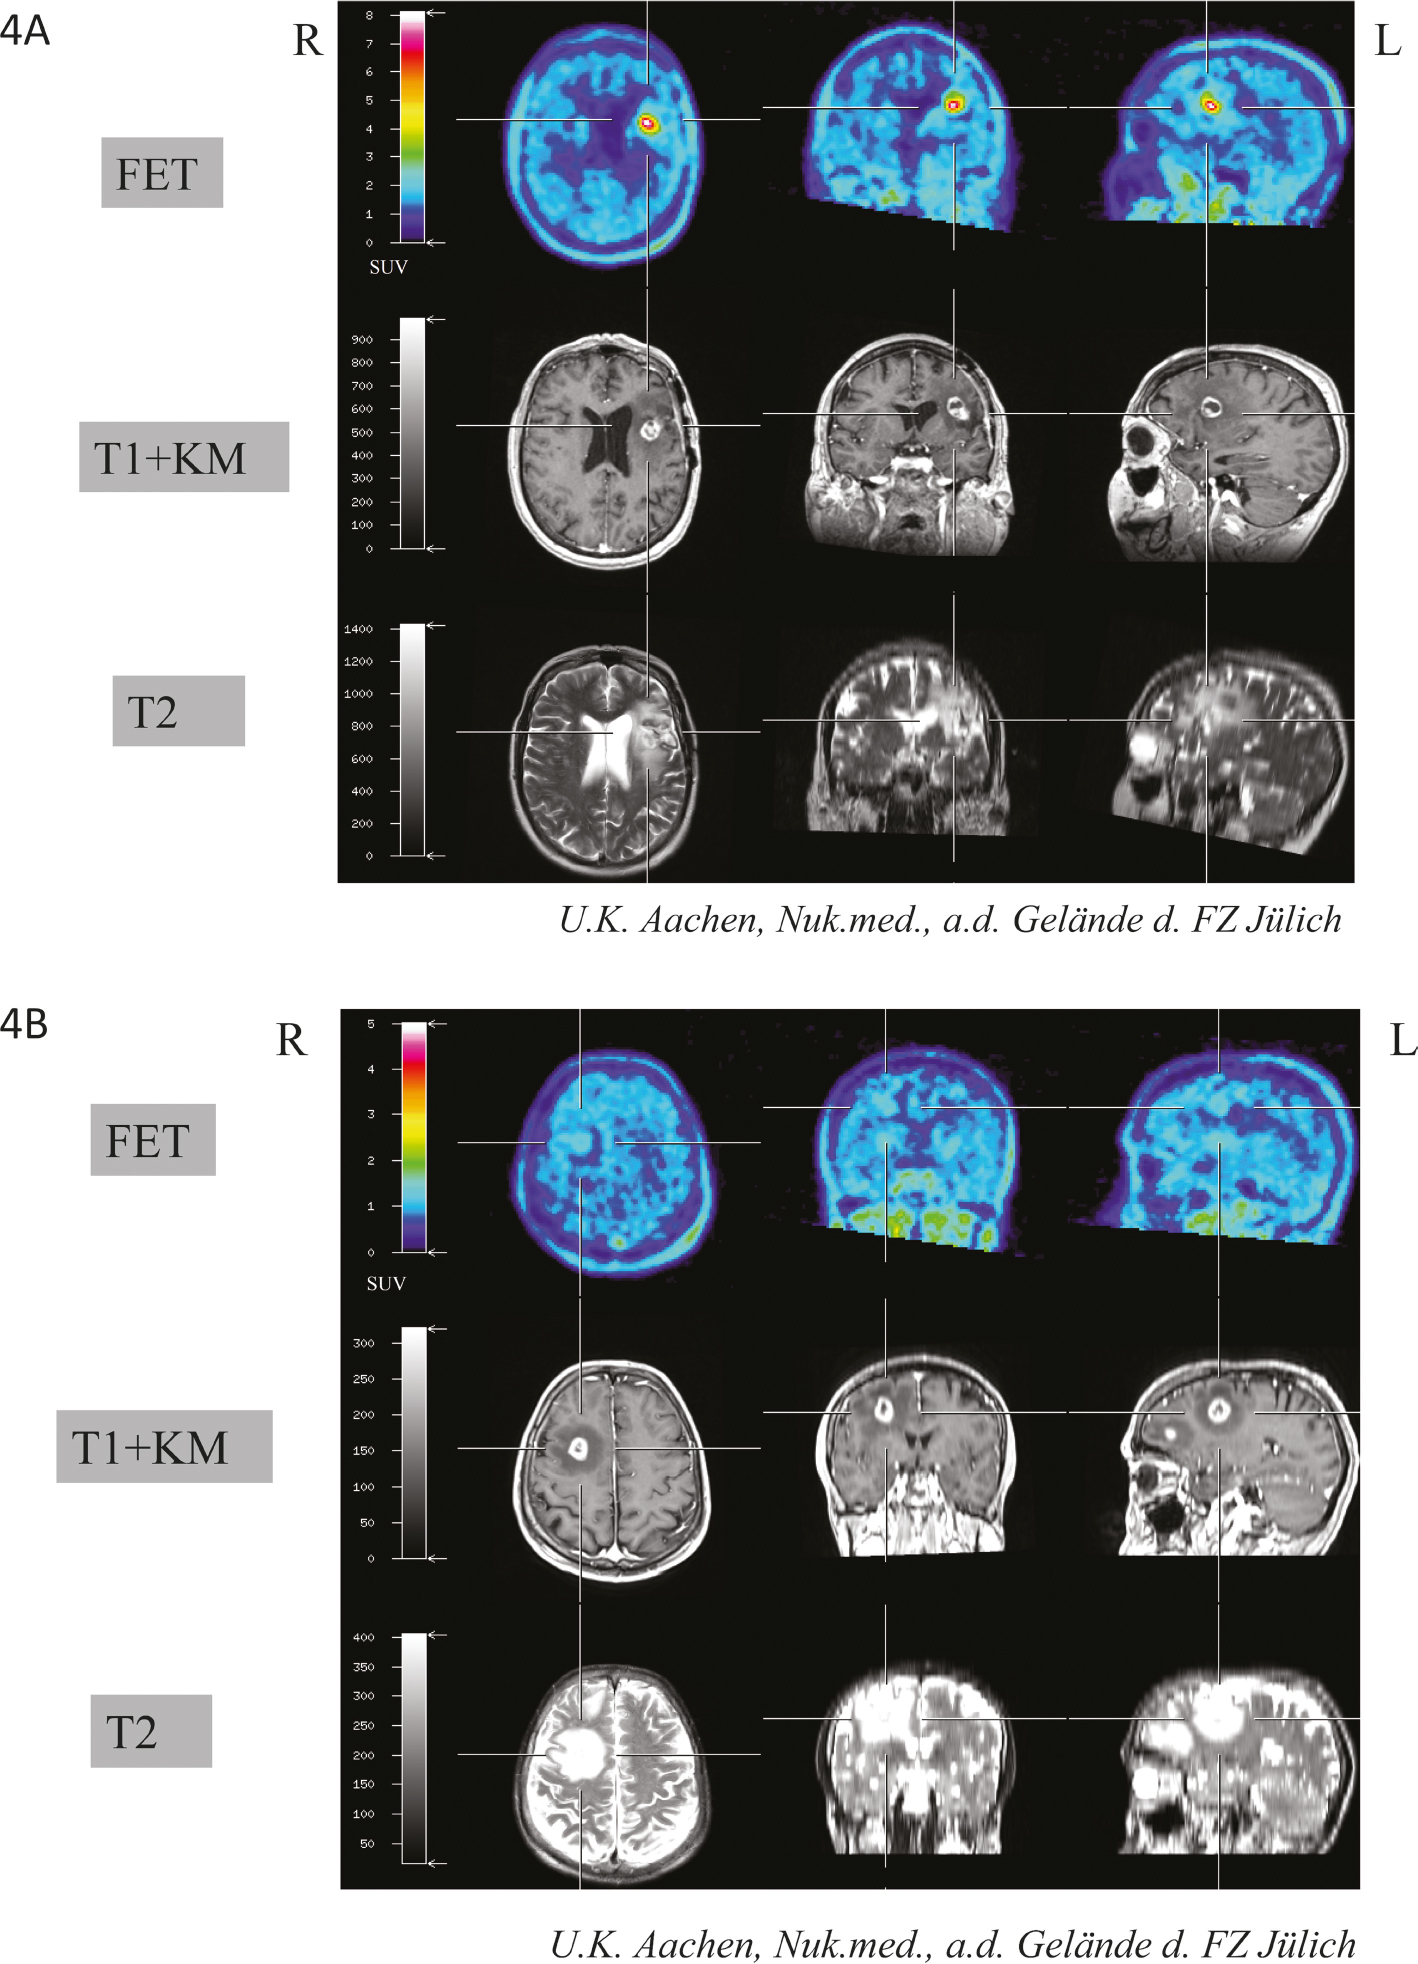

An advantage of 18F-FDG imaging in brain metastases includes the ability to identify metastases from a wide variety of primary tumor types due to high FDG avidity in many cancers and their brain metastases. A disadvantage of 18F-FDG imaging is the high background physiological uptake of FDG in the normal brain parenchyma, particularly the grey matter, which can obscure pathological FDG uptake of brain metastases that most commonly occur at the grey matter white matter junction. This results in a low tumor-to-background ratio that can reduce the sensitivity for detection of brain metastases. Furthermore, brain metastases tend to start as small lesions and PET has a relatively limited spatial resolution for lesions smaller than 1 cm and thus the sensitivity for detecting smaller lesions may be further reduced. Of note, however, lesions smaller than 1 cm can still be readily detected in some patients as demonstrated in Figure 1. Hence, in multiple studies with small and/or heterogeneous patient populations, the sensitivity and specificity of 18F-FDG PET for detecting brain metastases or differentiating tumor recurrence from treatment-related change can vary significantly. Galldiks et al. reviewed multiple studies and identified a sensitivity range of 40–95% and a specificity range of 50–100% (9). These findings may lead one to question the utility of FDG imaging for brain metastases, however in properly selected patients FDG PET imaging still has tremendous clinical value. Nonetheless, other PET molecular imaging agents may have advantages over FDG, and clinically relevant examples are included for review in this chapter.

Fig 1

Figure 1. MRI and 18F-FDG PET. Axial T1 contrast enhanced MRI (1A) and axial 18F-FDG PET (1B) of a patient with a small 6 mm right cerebellar brain metastasis from non-small cell lung carcinoma demarcated by solid arrows. Although there is relatively high background physiological uptake of 18F-FDG in the cerebellum, there is higher uptake in the brain metastasis above this background uptake.